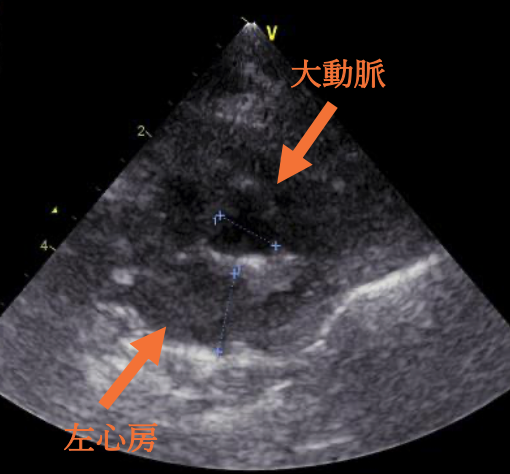

今回の⼼臓超⾳波検査では、 ⼤動脈へ流れる⾎液の速度がやや速くなっている所⾒が確認されました。現在、ねこちゃんに症状はありませんが、圧⼒が強い状態が続くと、⼼臓の筋⾁が厚くなったり不整脈を引き起こす可能性があるため、 お薬の量を調整しています。

肥⼤型⼼筋症とは、左⼼室の壁が厚くなってしまい、⾎液をうまく送り出せなくなる病気です。その中でも「閉塞性肥⼤型⼼筋症」とは、左室流出路(左⼼室の出⼝)が、厚くなった⼼筋や僧帽弁によって狭くなるタイプを指します。